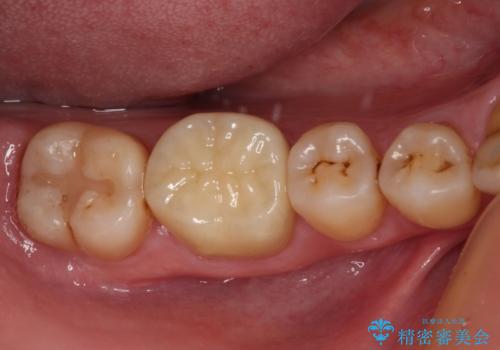

フルジルコニアクラウンは、やや光沢のある材質ですが、奥歯に装着した場合にはさほど気にならず、自然な口元の印象となりました。